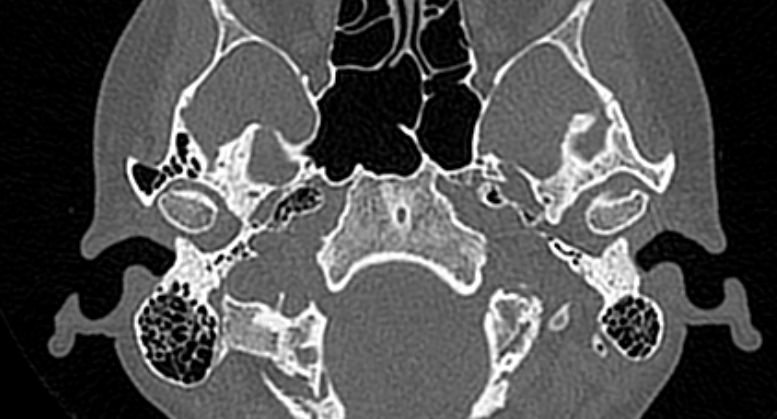

Наиболее точным и информативным методом диагностики костной патологии ВНЧС является мультиспиральная компьютерная томография. КТ относится к лучевым методам исследования, то есть для сканирования применяется рентгеновское излучение. В отличие от обычного рентгена томограф проводит одномоментно множество тончайших срезов исследуемой зоны, которые в дальнейшем проходят цифровую обработку. В результате получаются детальные снимки и трехмерные изображения области височно-нижнечелюстных суставов, которые позволяют проводить точную и достоверную диагностику.

Для оценки функции височно-нижнечелюстных суставов КТ-сканирование проводится в нескольких положениях: с открытым ртом и закрытым ртом. С помощью таких функциональных проб можно оценить положение суставной головки нижней челюсти при движениях нижней челюсти, выявить привычные вывихи и подвывихи суставов.

Компьютерная томография позволяет оценить состояние костных структур височно-нижнечелюстных суставов, так как рентгеновские лучи хорошо задерживаются костной тканью. Для повышения диагностических возможностей компьютерной томографии в ряде случаев дополнительно проводится контрастное усиление путем внутривенного введения йодсодержащего контрастного препарата. Эта методика применяется для улучшения визуализации мягких тканей, которые хуже видны при нативном исследовании.

С помощью КТ можно оценить состояние костной ткани суставных головок нижней челюсти, внутрисуставного мениска, суставной капсулы, связочного аппарата и жевательных мышц.

- Дегенеративно-дистрофические заболевания (артроз височно-нижнечелюстных суставов, который проявляется уменьшением просвета внутрисуставной щели, истончением хрящевой ткани, разрастанием остеофитов);